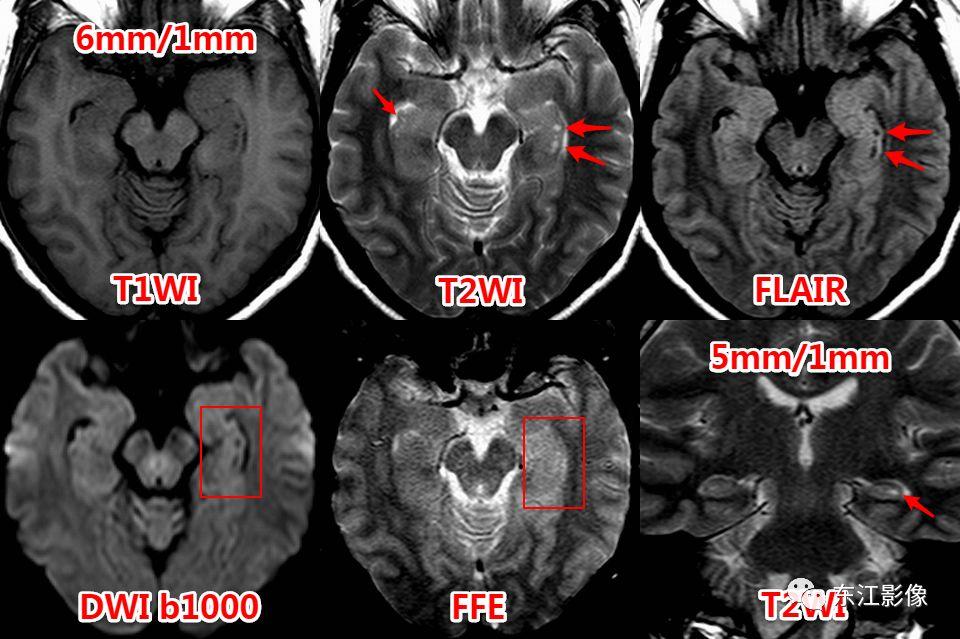

中脑急性梗死,与扩大的血管周围间隙比较。

血管周围间隙常见分布。

前穿质区VRS经典CT、MRI影像。

侧脑室顶区周围白质也是VRS的常见部位。

基底节区扩大的血管周围间隙,丘脑腔隙灶典型影像,均为脑小血管病影像学标志。